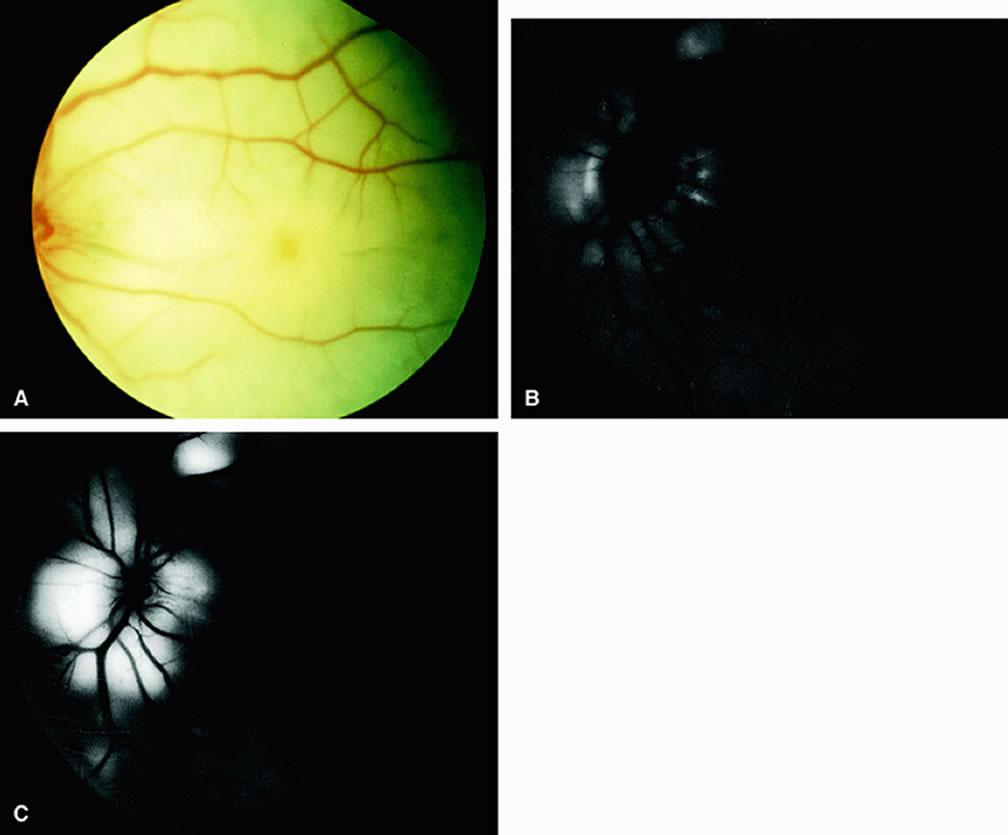

Clinically, acute ophthalmic artery obstructions differ from acute central retinal artery obstructions in that persons with the former often have no light perception and the retinal whitening appears more intense on examination.3 A cherry-red spot is often absent in eyes with acute ophthalmic artery obstruction, but its presence does not rule out the diagnosis (Fig. 3A). Electroretinography often reveals diminished amplitudes of both b- and a-waves that are caused by inner and outer retinal ischemia, respectively.3 In contrast, with a central retinal artery obstruction alone, the a-wave amplitude is usually normal and the b-wave amplitude is often diminished because of inner retinal ischemia.4

Fig. 3. A. Acute ophthalmic artery obstruction occurring secondary to a knife injury that severed the retinal and choroidal vessels posterior to the globe. Intense retinal whitening can be seen; a cherry-red spot is absent. B. Fluorescein angiogram of A taken at 55 seconds after injection reveals an absence of dye within the retina and most of the choroid. Mild peripapillary hyperfluorescence can be seen, presumably resulting from anastomoses between the episcleral, pial, and choroidal vessels in the vicinity of the optic disc. C. Increased peripapillary hyperfluorescence at 10.5 minutes after injection. (Brown GC, Magargal LE: Sudden occlusion of the retinal and posterior ciliary circulations in a youth. Am J Ophthalmol 88:690, 1979)

Fluorescein angiography of eyes with acute ophthalmic artery obstruction shows delayed filling of the retinal vessels and usually the choroidal vessels as well (see Fig. 3B and C). Focal, pinpoint areas of staining resulting from leakage of dye at the level of the retinal pigment epithelium can be seen in some instances. Diffuse staining is also occasionally observed. Prominent staining of the retinal vessels is usually absent with acute ophthalmic artery obstruction, although it can be seen with chronic ophthalmic artery obstruction.